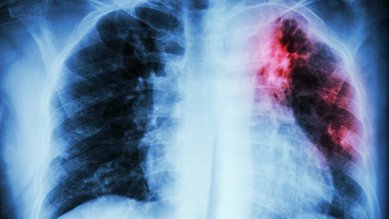

Lungenkrebs

Lungenkrebs gehört zu den häufigsten Krebsarten. In Deutschland erkranken pro Jahr etwa 57.000 Menschen an Lungenkrebs.